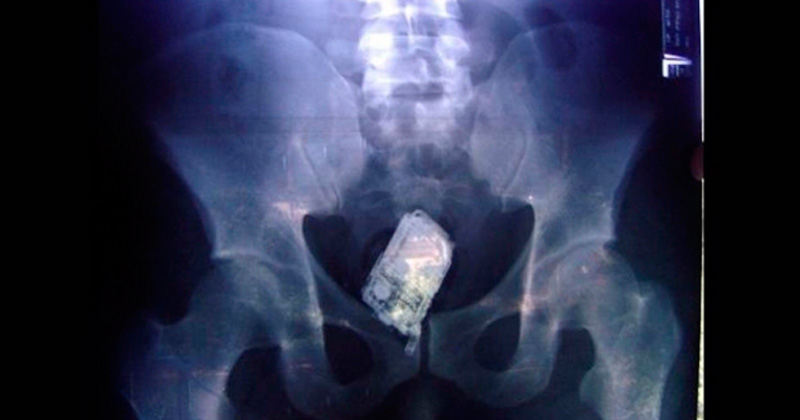

Reos brasileños guardaban celulares en sus estómagos y rectos

Uno de los implicados guardaba 10 aparatos en su estómago, por lo cual fue sometido a una cirugía